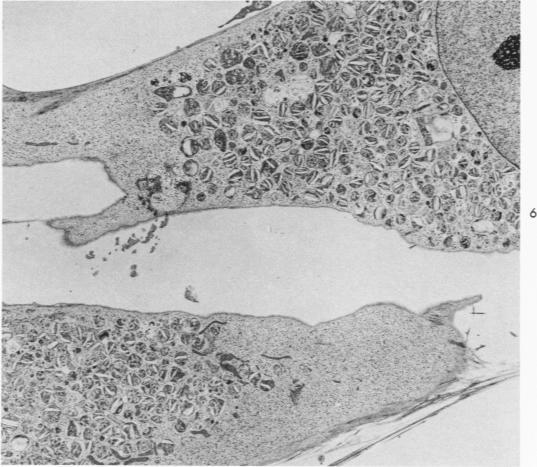

Cells derived from human atherosclerotic plaques and from arterial media were compared with cells obtained from human leiomyomata and myometrium with respect to growth behavior in long-term cell culture. None of numerous variations in culture media, including alterations of serum concentration and source, improved the rate of cell multiplication or in vitro longevity. Both uterine cell types, but neither arterial cell type, multiplied after tissue dissociation with enzymes (elastase, collagenase, hyaluronidase). The replicative life-span of each of eight samples of arterial plaque cells was equal to or less than that of the corresponding medial cells. A similar relationship was observed for eight paired sets of leiomyoma and myometrial cells. The results indicate that, under the conditions of culture in vitro, cells of a bona fide smooth muscle tumor have a finite replicative life-span and smooth muscle cells of atherosclerotic plaques behave in a similar manner.

就长期细胞培养中的生长行为而言,将源自人类动脉粥样硬化斑块和动脉中层的细胞与源自人类平滑肌瘤和子宫肌层的细胞进行了比较。在包括血清浓度和来源改变在内的多种培养基变化中,没有一种能提高细胞增殖率或体外存活时间。两种子宫细胞类型在经酶(弹性蛋白酶、胶原酶、透明质酸酶)解离组织后都会增殖,但两种动脉细胞类型都不会。八个动脉斑块细胞样本中每个样本的复制寿命等于或小于相应中层细胞的复制寿命。八对平滑肌瘤和子宫肌层细胞也观察到类似关系。结果表明,在体外培养条件下,真正的平滑肌肿瘤细胞具有有限的复制寿命,动脉粥样硬化斑块的平滑肌细胞表现方式类似。